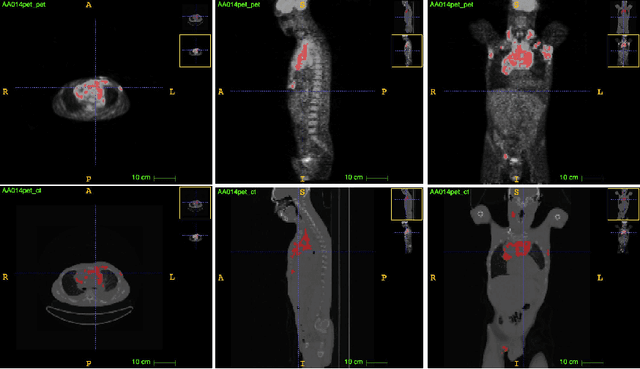

Abstract:Single-modality medical images generally do not contain enough information to reach an accurate and reliable diagnosis. For this reason, physicians generally diagnose diseases based on multimodal medical images such as, e.g., PET/CT. The effective fusion of multimodal information is essential to reach a reliable decision and explain how the decision is made as well. In this paper, we propose a fusion framework for multimodal medical image segmentation based on deep learning and the Dempster-Shafer theory of evidence. In this framework, the reliability of each single modality image when segmenting different objects is taken into account by a contextual discounting operation. The discounted pieces of evidence from each modality are then combined by Dempster's rule to reach a final decision. Experimental results with a PET-CT dataset with lymphomas and a multi-MRI dataset with brain tumors show that our method outperforms the state-of-the-art methods in accuracy and reliability.

Abstract:An automatic evidential segmentation method based on Dempster-Shafer theory and deep learning is proposed to segment lymphomas from three-dimensional Positron Emission Tomography (PET) and Computed Tomography (CT) images. The architecture is composed of a deep feature-extraction module and an evidential layer. The feature extraction module uses an encoder-decoder framework to extract semantic feature vectors from 3D inputs. The evidential layer then uses prototypes in the feature space to compute a belief function at each voxel quantifying the uncertainty about the presence or absence of a lymphoma at this location. Two evidential layers are compared, based on different ways of using distances to prototypes for computing mass functions. The whole model is trained end-to-end by minimizing the Dice loss function. The proposed combination of deep feature extraction and evidential segmentation is shown to outperform the baseline UNet model as well as three other state-of-the-art models on a dataset of 173 patients.

Abstract:Lymphoma detection and segmentation from whole-body Positron Emission Tomography/Computed Tomography (PET/CT) volumes are crucial for surgical indication and radiotherapy. Designing automatic segmentation methods capable of effectively exploiting the information from PET and CT as well as resolving their uncertainty remain a challenge. In this paper, we propose an lymphoma segmentation model using an UNet with an evidential PET/CT fusion layer. Single-modality volumes are trained separately to get initial segmentation maps and an evidential fusion layer is proposed to fuse the two pieces of evidence using Dempster-Shafer theory (DST). Moreover, a multi-task loss function is proposed: in addition to the use of the Dice loss for PET and CT segmentation, a loss function based on the concordance between the two segmentation is added to constrain the final segmentation. We evaluate our proposal on a database of polycentric PET/CT volumes of patients treated for lymphoma, delineated by the experts. Our method get accurate segmentation results with Dice score of 0.726, without any user interaction. Quantitative results show that our method is superior to the state-of-the-art methods.

Abstract:PET and CT are two modalities widely used in medical image analysis. Accurately detecting and segmenting lymphomas from these two imaging modalities are critical tasks for cancer staging and radiotherapy planning. However, this task is still challenging due to the complexity of PET/CT images, and the computation cost to process 3D data. In this paper, a segmentation method based on belief functions is proposed to segment lymphomas in 3D PET/CT images. The architecture is composed of a feature extraction module and an evidential segmentation (ES) module. The ES module outputs not only segmentation results (binary maps indicating the presence or absence of lymphoma in each voxel) but also uncertainty maps quantifying the classification uncertainty. The whole model is optimized by minimizing Dice and uncertainty loss functions to increase segmentation accuracy. The method was evaluated on a database of 173 patients with diffuse large b-cell lymphoma. Quantitative and qualitative results show that our method outperforms the state-of-the-art methods.